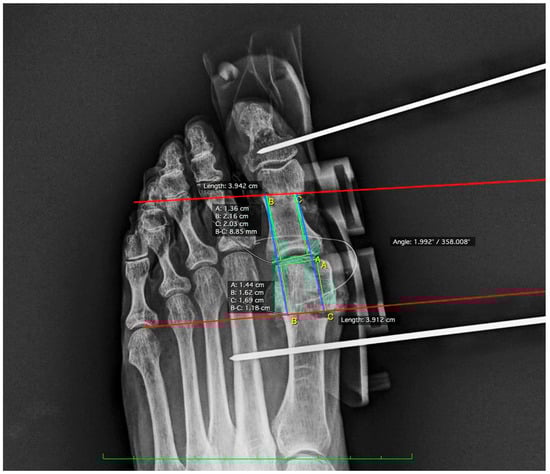

To evaluate the results, post-operative radiographs were taken with simulated loading. The images obtained were analyzed with Osirix MD Software (Pixmeo, Bernex, Switzerland). In measurement 1, the distance from the medial proximal end of the Akin osteotomy to the base of the proximal phalanx at the joint line was measured. This parameter is key to assessing the accuracy of the osteotomy alignment with respect to the surrounding articular structures. In measurement 2, the distance from the proximal lateral end of the Akin osteotomy to the base of the proximal phalanx at the joint line was determined. This measurement complements the first measurement by providing a complete perspective of the osteotomy orientation. Measurement 3 consisted of calculating the distance from the medial distal end of the Reverdin osteotomy to the articular interline formed by the head of the first metatarsal. In measurement 4, the distance from the distal lateral end of the Reverdin osteotomy to the articular interline formed by the head of the first metatarsal and the base of the proximal phalanx was measured to verify symmetry and correct placement of the osteotomy on the lateral side. Finally, angle measurement evaluated the angle formed by the two previous osteotomies (see Figure 2).

Figure 2. Post-surgical radiographic measurements lines using the Osirix program.